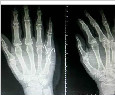

目的:比较微型钢板与克氏针内固定术治疗掌指关节周围骨折患者的效果。方法: 回顾性分析 2020 ...